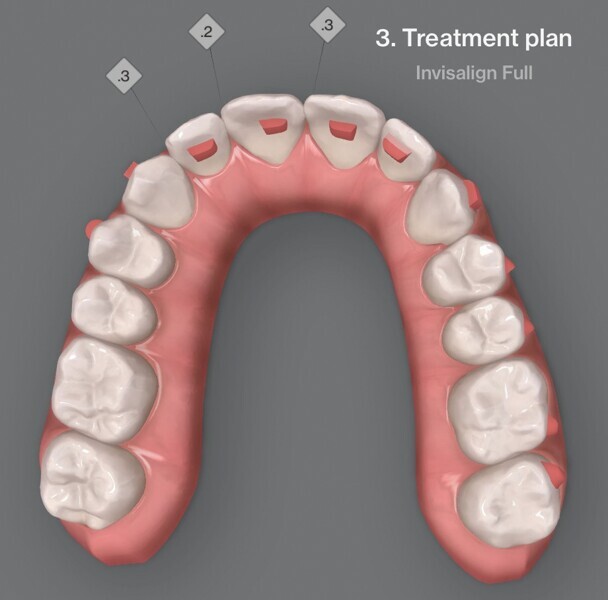

Fig. 4a : Premier résultat prévu par simulation ClinCheck.

Fig. 4b : Premier résultat prévu par simulation ClinCheck.

Fig. 4c : Premier résultat prévu par simulation ClinCheck.

Fig. 4d : Premier résultat prévu par simulation ClinCheck.

Fig. 4e : Premier résultat prévu par simulation ClinCheck.

Le premier plan de traitement par simulation ClinCheck prévoit 53 aligneurs, afin de réaliser une distalisation séquentielle postérieure d’environ 4 mm sur le côté gauche du maxillaire, une expansion de 2 mm par quadrant et un alignement dans la zone antérieure. Il prévoit également une réduction interproximale (RIP) sélective de 0,25 mm sur chaque face des dents de l’arcade mandibulaire, et de 0,10 mm à 0,15 mm pour les dents de l’hémiarcade maxillaire droite (Fig. 4). Une application topique de fluorure est planifiée dans les zones soumises à une RIP après la procédure. Des élastiques de classe II sont utilisés du côté gauche pour faciliter la distalisation. La fréquence de changement des aligneurs est fixée à sept jours et elle sera ramenée à cinq jours par la suite. Un accélérateur de traitement orthodontique par vibrations est utilisé, afin d’augmenter la vitesse et la prédictibilité des mouvements dentaires. Le traitement n’envisage pas l’utilisation d’aligneurs de surcorrection.